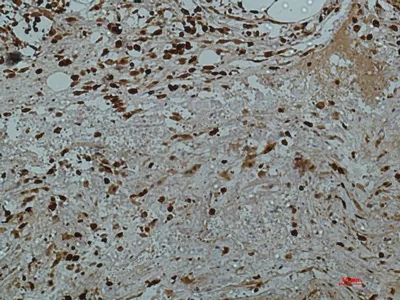

Smad3(4C9)Mouse Monoclonal Antibody

Cat: AMM17995

Size1:50μl Price1:$118

Size2:100μl Price2:$220

Size3:500μl Price3:$980

Size2:100μl Price2:$220

Size3:500μl Price3:$980